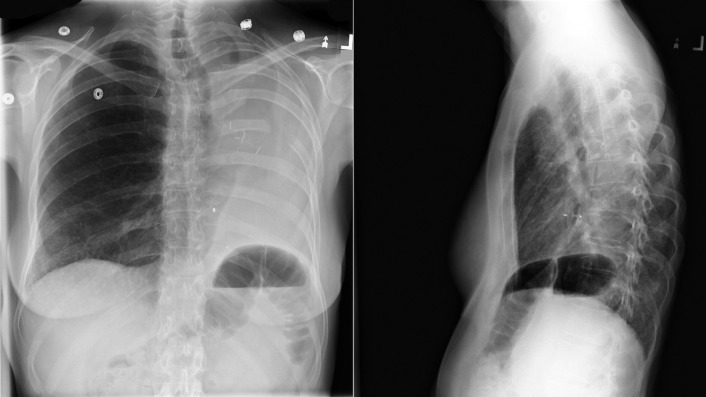

Left-to-right shunts initially result in volume overload of the chambers carrying the shunt volume, causing enlargement of the volume-overloaded chambers and an increase in pulmonary blood flow. If the amount of pulmonary blood flow is sufficiently high, obliterative disease of the pulmonary arterioles develops (“pulmonary vascular disease”), resulting in pulmonary hypertension. The chest radiographic appearance of pulmonary hypertension is one of centralization of pulmonary flow and accelerating enlargement of the right-sided chambers.

See Figures 18-5 to 18-31 . Possible findings are discussed in the following sections.